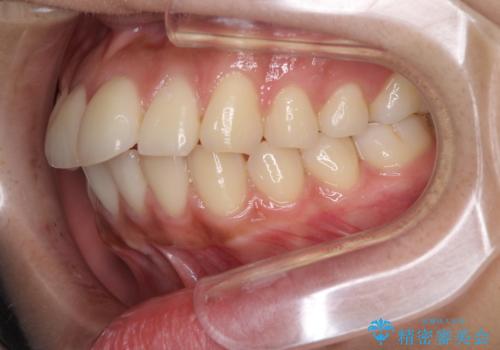

横顔をすっきりさせたい 下の前歯が1本少ない方の変則的な抜歯矯正

口元の突出感がありと、下顎の前歯が1本欠損していました。

上顎の前から両側の前から4番目の歯と、下あごの前歯を1本抜歯して、口元をすっきりさせる計画としました。